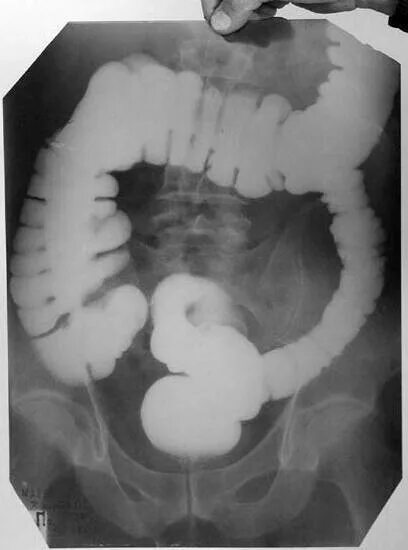

Болезнь гершпрунга у взрослых